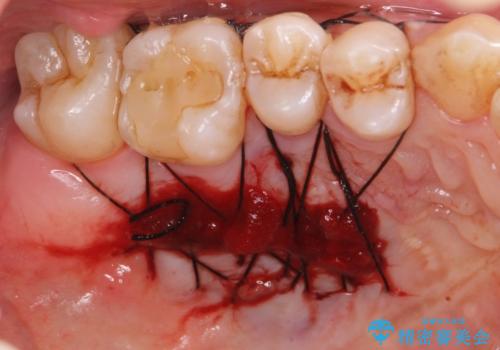

- 矯正前に下顎前歯の歯肉退縮の改善と予防のために歯肉移植を行った症例です。

上顎口蓋部から結合組織を採取し、下顎前歯部に移植しました。

- 外科手術のため、術後に痛みや腫れ、違和感を伴います